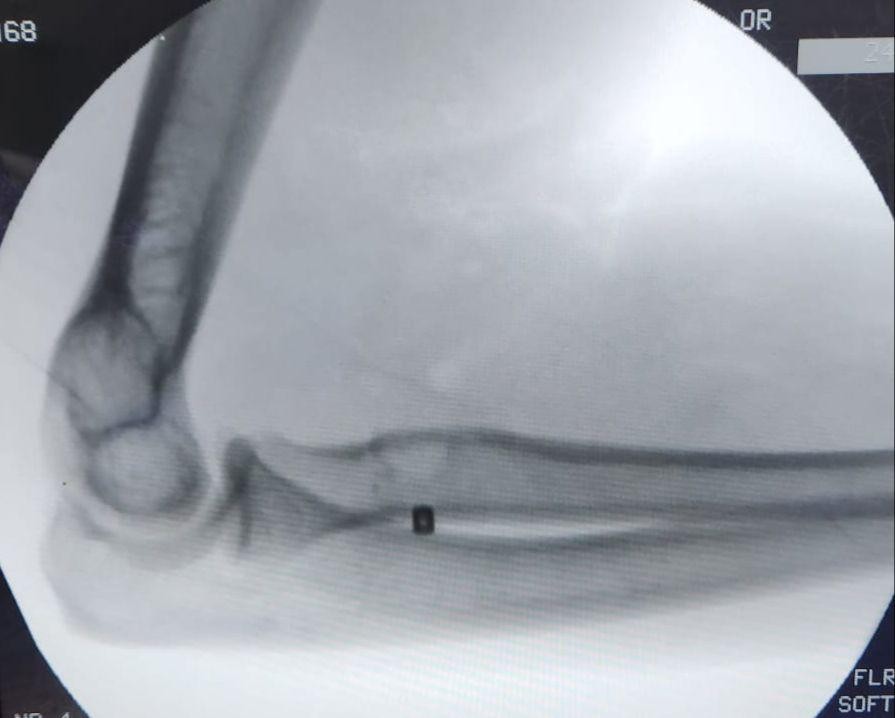

تمكن فريق طبي في جراحة العظام بمستشفى الملك فهد بجدة من إجراء عملية لمريض في الأربعين من عمره ، و إعادة وتره المقطوع ، نتيجة لتعرضه قبل شهر لقطع في العضلة التي تسمى البايسيبس ، و قد تمكن الفريق من إعادة و تثبيت الوتر المقطوع لمكانه بقيادة الدكتور شهاب بوسطجي استشاري الزمالة الألمانية في جراحة العظام و إصابة الملاعب بمستشفى الملك فهد بجدة .

و أشار الدكتور بوسطجي رئيس الفريق الطبي الذي أجرى العملية أنه قد تم إجراء الفحوصات اللازمة للمريض قبل العملية من أشعة رنين مغناطيسي ، مضيفاً إلى أن هذا النوع من العمليات يُعد نادراً و من العمليات الدقيقة جداً التي تحتاج وقتاً للعودة لوضعها الطبيعي .